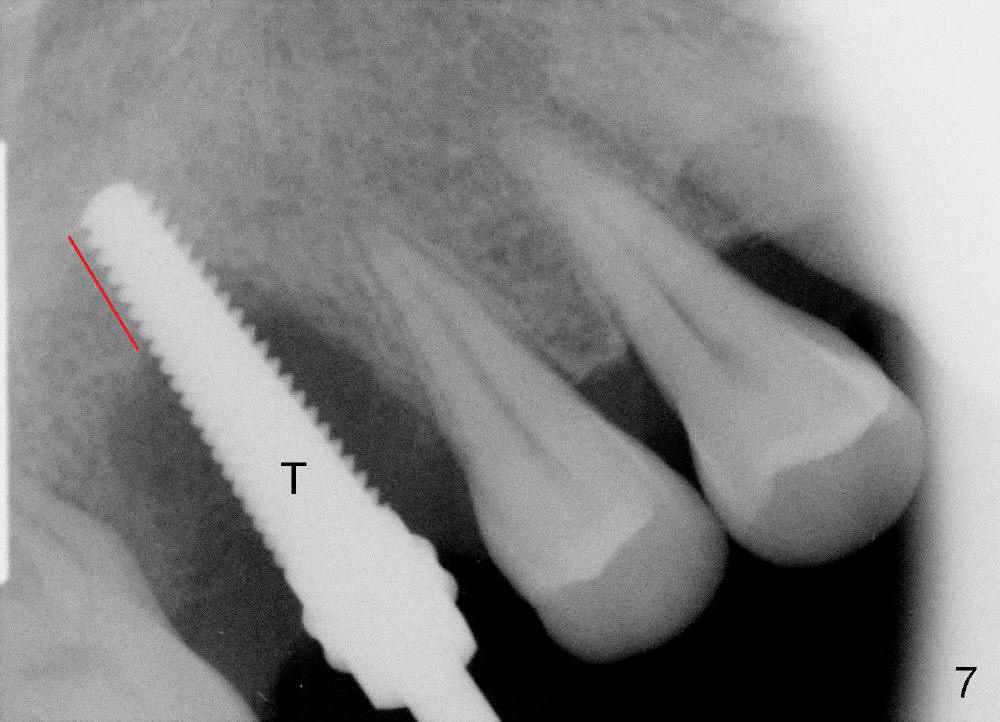

The tooth #3 has severe periodontitis with probably endodontic lesion (Fig.1,2). The patient is a 43-year-old man with apprehension of dentistry. An acute infection causes pain and tooth shift (Fig.4,5). A 7x17 mm immediate implant is planned (Fig.3). The palatal socket is shallow (Fig.6 P), corresponding to severe recessive palatal root (Fig.5 P). The osteotomy is created mainly in the buccal socket (Fig.6 B), exactly in the lingual slope of the septum. Initially osteotomes are used, followed by tap placement (Fig.7 T (4.5x20 mm at the depth of 17 mm). When the implant is placed as planned (Fig.8 I), there is more vertical contact (Fig.8 red line) than that associated with the tap (Fig.7 red line). The corresponding insertion torque is between 50 and 60 Ncm. There is only one small gap buccally, which is filled with bone graft (Fig.9 <). After the insertion of a short abutments with vertical slots (Fig.9,10 A), perio dressing is used to cover the wound. The palatal socket is expected to heal uneventfully (Fig.10 P). In fact, it does in 7 days (Fig.12 P); the bone graft in the mesiobuccal aspect is healing and stabilized (Fig.11 <). By two weeks postop, the mesiobuccal socket has healed (Fig.13 <). With removal of a diseased tooth, our body has amazing power to heal.